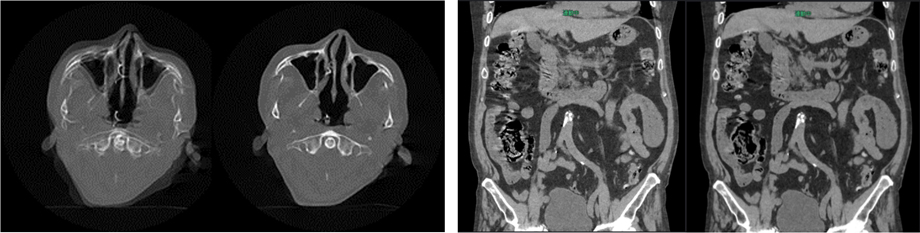

CT撮影時の被写体の動きによる画像のブレを低減する技術StillShot*2は、適用範囲を胸部、心臓に加え、頭部、腹部へと拡げた。撮影中の被検者の動きによる画像のブレを補正して、アーチファクトの少ない画像を作成する。

StillShotは収集したRaw Dataから被写体の動く方向と量を4次元的に算出する際に、体軸方向の連続性を広範囲に維持することでブレの少ない画像を提供する。胸部、心臓だけでなく、頭部や腹部においても、撮影中の被検者の動きによる画像のブレを補正して、アーチファクトの少ない画像を作成する。